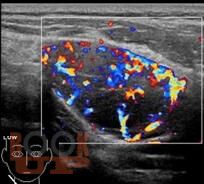

Мультипараметрическое ультразвуковое исследование образований шеи, больших слюнных желез и лимфатических узлов

Учебное пособие посвящено ультразвуковой диагностике образований шеи, больших слюнных желез и лимфатических узлов. Подробно рассмотрены методологические аспекты применения мультипараметрического ультразвукового исследования слюнных желез и лимфатических узлов в норме и при различных заболеваниях, редкой патологии - врожденной сосудистой мальформации на шее. В конце пособия приведены вопросы и ответы для самоконтроля.